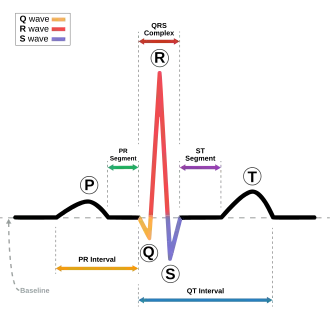

The ECG

E.C.G stands for Electrocardiogram and represents the electrophysiology of the heart. Cardiac electrophysiology is the science of the mechanisms, functions, and performance of the electrical activities of specific regions of the heart. The ECG is the recording of the heart's electrical activity as a graph. The graph can show the heart's rate and rhythm, it can detect enlargement of the heart, decreased blood flow, or the presence of current or past heart attacks. ECG's are inexpensive, Non-invasive, quick, and painless. Depending on the results, the patient’s medical history, and a physical exam; further tests or a combination of medications and lifestyle changes may be ordered.

Electrocardiogram

• The P is the atrial depolarization

• QRS is the ventricular depolarization, as well as atrial repolarization.

• T is the ventricular repolarization

5. When reading an EKG, this letter shows the depolarization from the AV node down to the AV bundle

- A) S

- B) P

- C) U

- D) T

- E) Q

6. The T wave in an EKG shows

- A) Resting potential

- B) Atrial depolarization

- C) SA node excitation

- D) Ventricle repolarization

- E) Purkinje Excitation